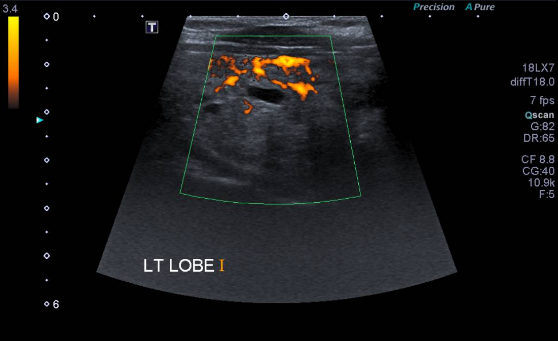

Sonar

Ultrasound imaging, also called sonography, uses sound waves to produce ultrasound images of the inside of the body. An instrument called a transducer emits high-frequency sound, inaudible to human ears, and then records the echoes as the sound waves bounce back to determine the size, shape, and consistency of soft tissues and organs. It is used to help diagnose the causes of pain, swelling and infection in the body's internal organs, joints and tendons. Doppler ultrasound is used to evaluate the arteries and veins to diagnose obstructions or blood clots also vascular malformities. Ultrasound is safe, noninvasive, and does not use ionizing radiation. Ultrasound is useful for guiding biopsy procedures.